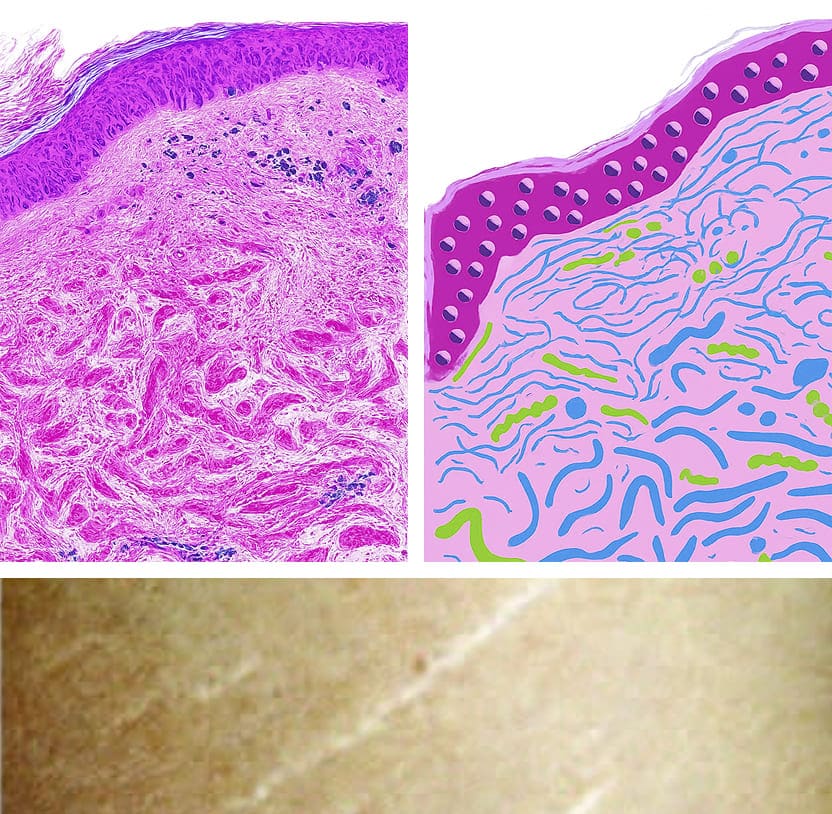

Einführung in feine Linien & Falten

Considered a part of the aging process of the skin. This aging process is accompanied with structural and functional changes in extracellular matrix components such as collagen and elastin which can result in the appearance of fine lines and wrinkles.

Wirkmechanismus:

- Induktion des Wundheilungsprozesses und Stimulation der natürlichen Wachstumsfaktoren der Haut

- Erhöhung der epidermalen Dicke und des Tropoelastingehalts

- Zuführen der Hautkollagentypen I, III und VII